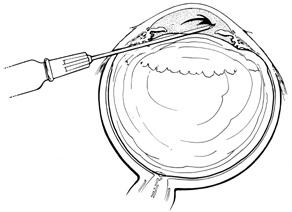

Medical attempts to lower pressure usually are effective only for relatively small buckles. For circumferential buckles extending more than one quadrant, intraocular volume must be removed surgically. In phakic eyes, anterior chamber paracentesis can remove up to 0.3 to 0.4 mL of aqueous at one time. Paracentesis is performed under magnification at the limbus with a blade, which is passed in a shelved manner through the cornea, entering the anterior chamber over the iris to protect the lens. The blade then is rotated, thereby opening the wound to allow aqueous to egress. The depth of the anterior chamber is closely monitored to prevent damage to the lens. When enough drainage has been obtained, the blade is turned back to its original entering position. This closes the corneal wound and minimizes the chance of iris incarceration as the blade is removed. The corneal wound is self-sealing (Fig. 34). This technique is effective also in pseudophakic patients with posterior chamber intraocular lenses and intact posterior capsules or capsulotomies sealed by the intraocular lens. Alternatively, a 30-gauge needle can be used to remove aqueous.

Fig. 34. Anterior chamber paracentesis technique using limbal approach.